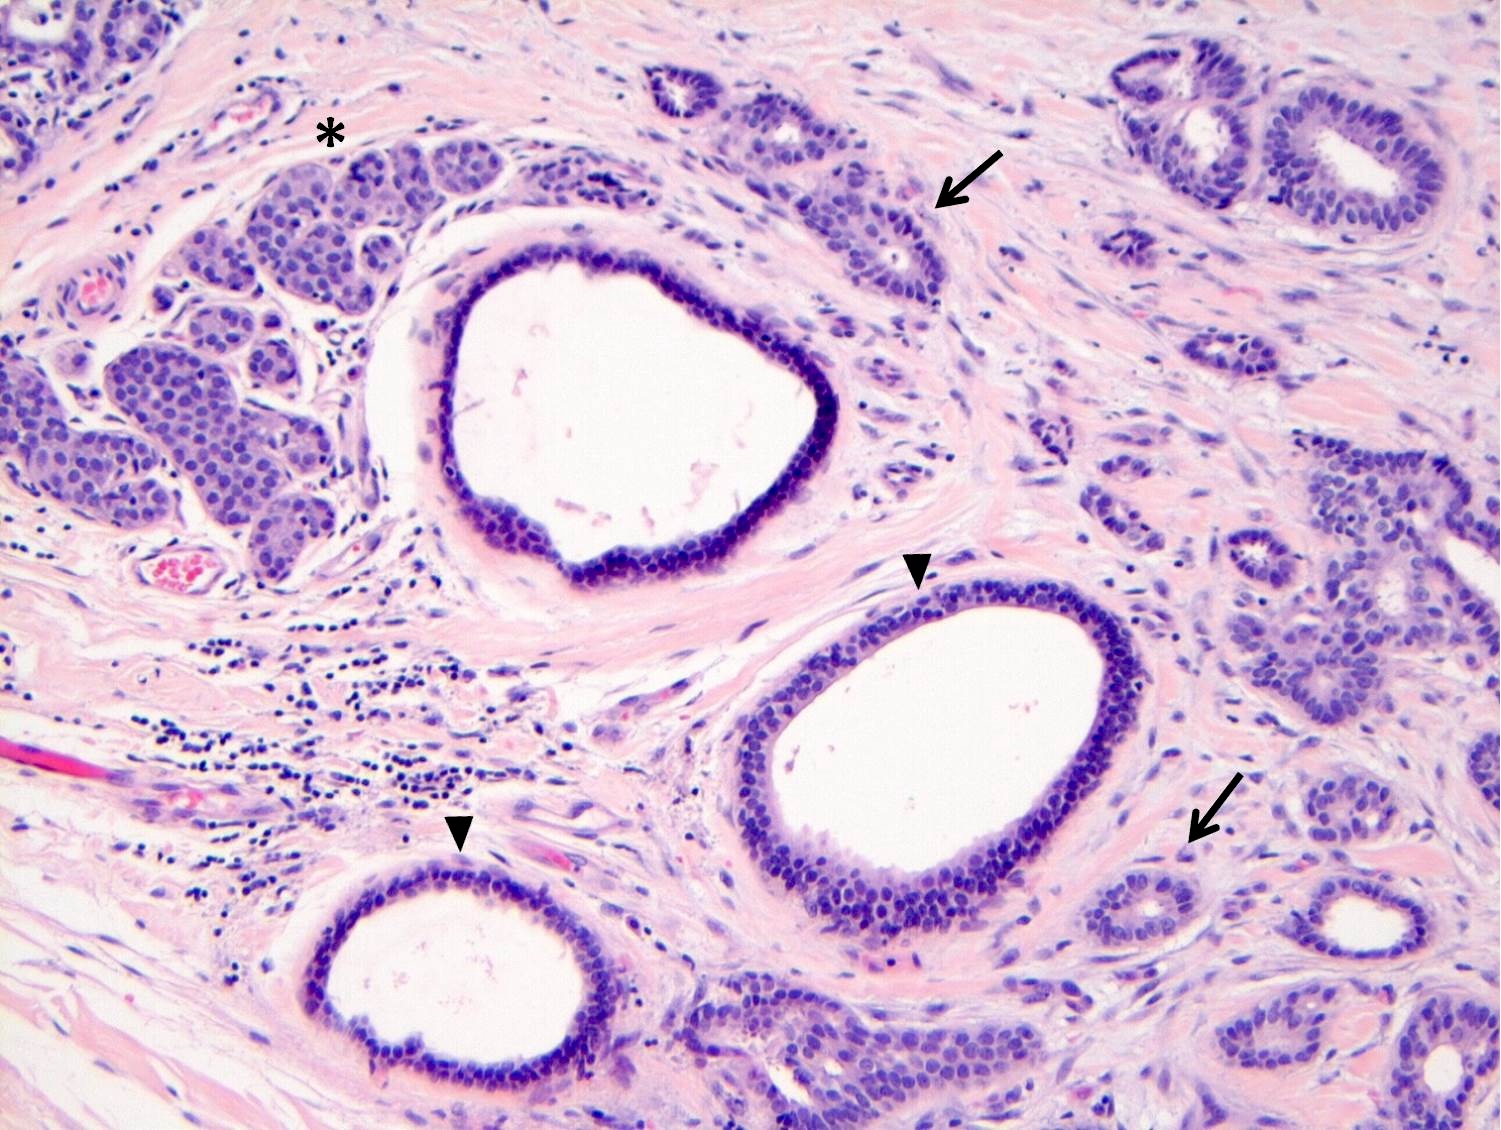

Microscopic (histologic) description

- LCIS involves the terminal duct lobular unit (TDLU), filling and distending acini

- > 50% of the acini in a TDLU must be filled and expanded to qualify as LCIS; otherwise, called atypical lobular neoplasia

- Lobular distention is defined as the presence of ≥ 8 cells in the cross sectional diameter of an acinus

- Involved lobules may be compared with uninvolved lobules to estimate the degree of distension

- ALH only partially involves the lobule by filling up the acini without significant distention

- LCIS most often involves lobules but may also grow along the basement membrane of ducts (i.e., pagetoid spread)

- LCIS may secondarily involve (or arise in) sclerosing adenosis, radial scar, fibroadenoma, collagenous spherulosis or papilloma

- Classic LCIS cells are monomorphic, evenly spaced, loosely cohesive and do not show polarization or gland formation

- Type A: nuclei are small to slightly enlarged (1 - 1.5x size of lymphocyte) with uniform round nuclei and inconspicuous nucleoli

- Type B: nuclei larger (2x size of lymphocyte), more abundant cytoplasm and more prominent nucleoli

- Type A and B cells can coexist in the same lesion

- Cytoplasm of LCIS cells is typically pale to lightly eosinophilic with indistinct cell borders

- In almost all cases of LCIS, at least some cells contain intracytoplasmic vacuoles or lumina, which may contain an eosinophilic globule; this feature is not specific to LCIS

- Outer layer of myoepithelial cells is retained in the acini and ducts involved but it may be attenuated

Microscopic (histologic) images

Contributed by Anna Biernacka, M.D., Ph.D.